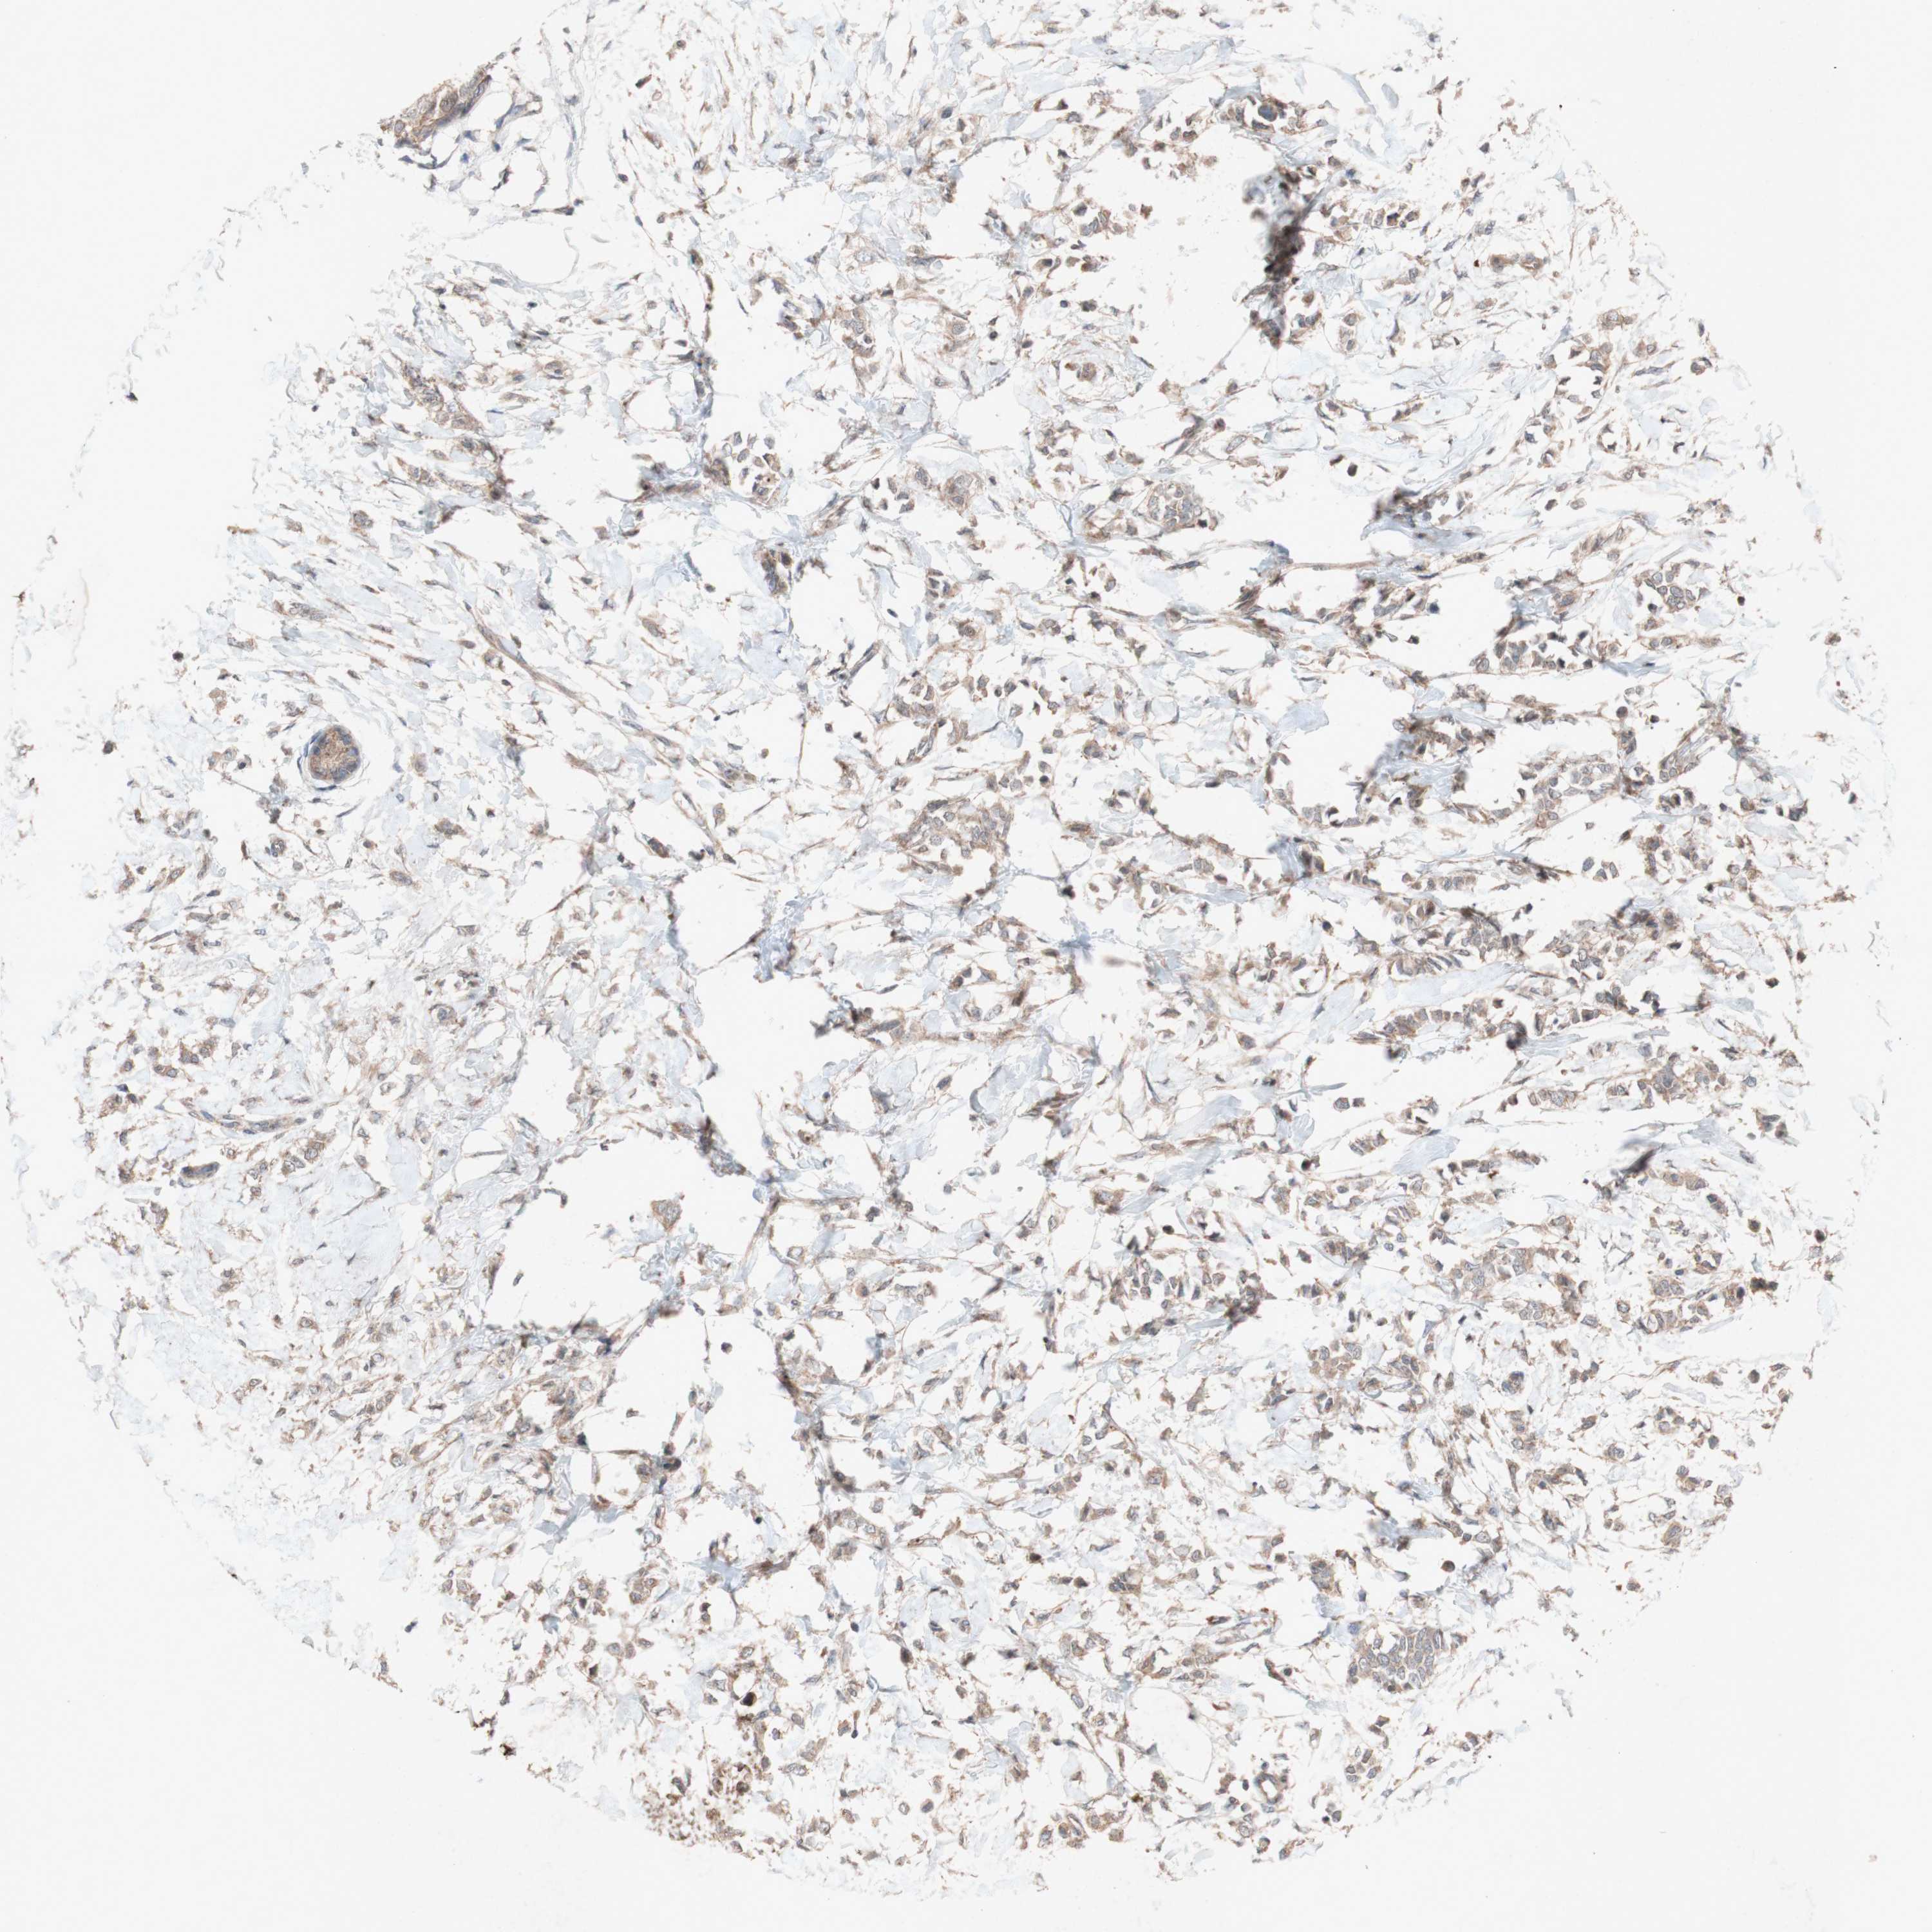

BRCA TCGA BRCA VALIDATION PROTEIN EXPRESSION

ANTIBODIES

AND

VALIDATION